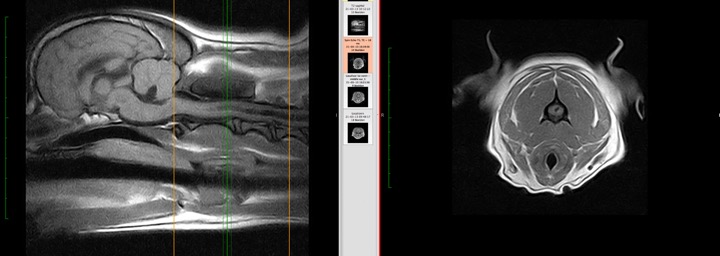

Neurologie is de tak van de geneeskunde die zich bezighoudt met de diagnose en behandeling van aandoeningen van het zenuwstelsel. Dit omvat de hersenen, het ruggenmerg, de zenuwen en de spieren. Een neuroloog is een arts die gespecialiseerd is in deze aandoeningen.

- Multiple sclerose (MS): MS is een auto-immuunziekte die de hersenen en het ruggenmerg aantast. Neurologen spelen een sleutelrol bij de diagnose, behandeling en het beheer van MS.

Aandoeningen van het ruggenmerg

Neurologen behandelen ook aandoeningen van het ruggenmerg, zoals:

- Ruggenmergletsel: Dit kan worden veroorzaakt door trauma of ziekte. Neurologen zijn betrokken bij de diagnose, behandeling en revalidatie.

- Spinale stenose: Dit is een vernauwing van het wervelkanaal, wat druk op het ruggenmerg kan veroorzaken.